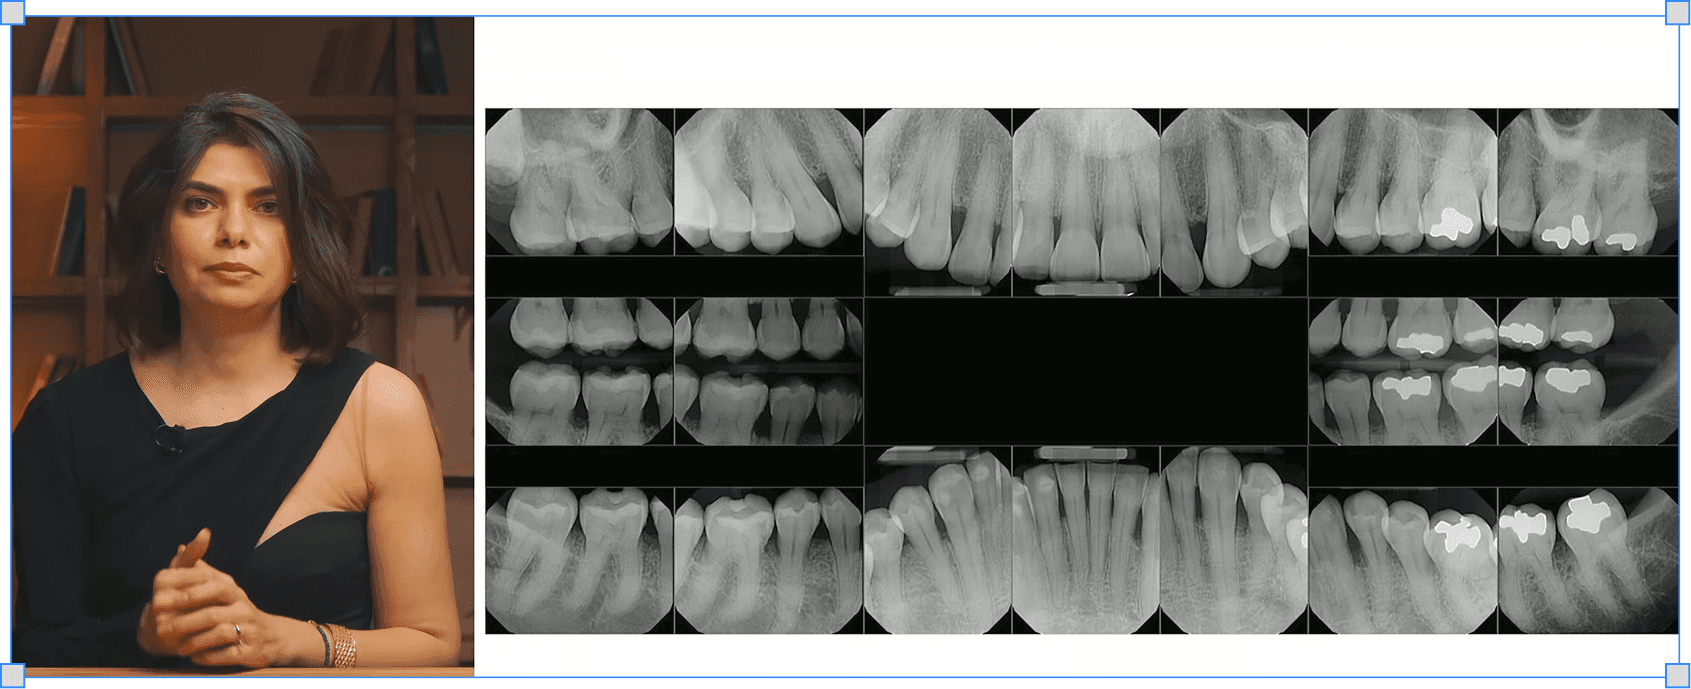

Як вибрати рентген для діагностики пародонтиту

Коли що показує більше — і чому відповідь не завжди на користь КТ

→ Бачиш деструкцію в деталях і відстежуєш динаміку